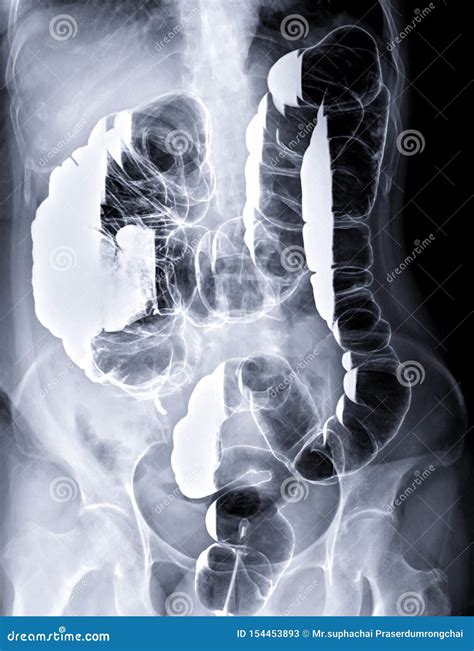

• Colonoscopies: This position is often used during colonoscopies to provide better access to the colon and rectum.

• Diagnostic Imaging: This positioning is also used in diagnostic imaging procedures such as CT scans and MRIs to provide better visualization of the targeted area.